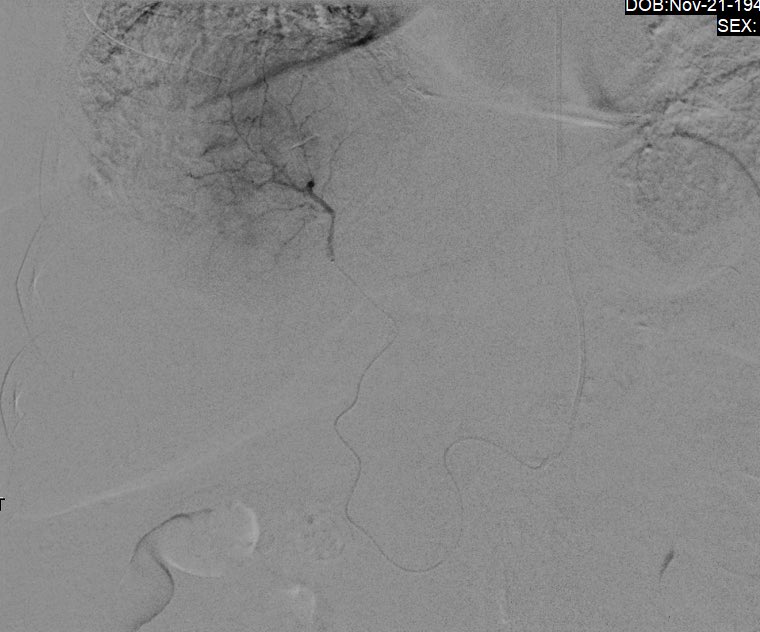

should be an AWESOME outcome #irad

Patient with seg4 HCC and celiac axis atherosclerotic occlusion (and aortioiliac disease). Difficult navigation via SMA collateral to GDA and finally seg4 branch of LHA #Y90. Hoping for a great outcome @MoffittNews @NaineshParikhMD Intra-op CTA @SiemensUSA Maestro @MeritMedical